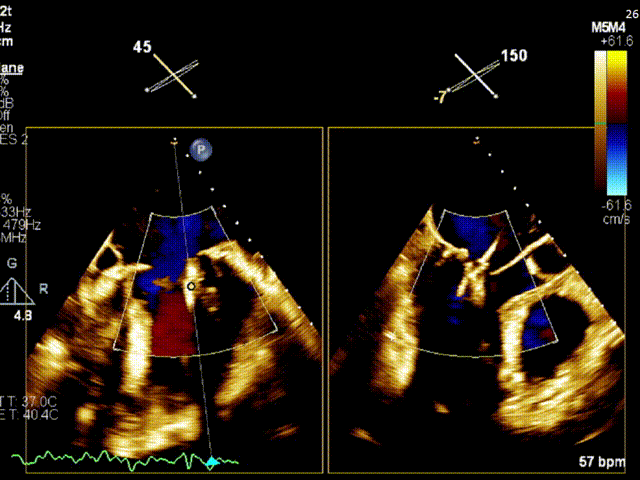

术前TEE评估

经食道超声提示,患者二尖瓣P1 commissural脱垂、腱索断裂合并重度反流(Carpentier II型/DMR4+)。

二尖瓣后瓣环明显钙化;主动脉瓣轻度钙化;三尖瓣中度功能性反流(FTR2+)。左房明显扩大;左室壁非对称性肥厚,以室间隔基底段肥厚为著(HOCM)。左室整体收缩功能正常。

二尖瓣环AP径33mm,二尖瓣后瓣环明显钙化,房间隔拟穿刺高度40mm;二尖辦脱垂宽度5.7mm,脱垂高度7.7mm,二尖瓣1区前叶长度29mm,后叶长度19mm,二尖瓣2区前叶长度23mm,后叶长度14mm,MVA=4.0cm²。

术前1区X-Plane反流情况